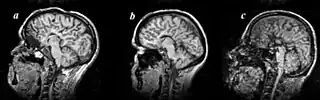

Colpocephaly is characterized by disproportionately large occipital horns of the lateral ventricles (also frontal and temporal ventricles in some cases). MRI and CT scans of patients demonstrate abnormally thick gray matter with thin poorly myelinated white matter. This happens as a result of partial or complete absence of the corpus callosum. Corpus callosum is the band of white matter connecting the two cerebral hemispheres. The corpus callosum plays an extremely important role in interhemispheric communication, thus lack of or absence of these neural fibers results in a number of disabilities.[12]

The lemon sign on CT scans of patients refers to the shape of the fetal skull when the frontal bones lose their normal convex contour and appear flattened or inwardly scalloped. This gives the skull a shape similar to that of a lemon. The sign is seen on transverse sonograms of the fetal cranium obtained at the level of the ventricles. A special case is found in literature where lissencephaly, colpocephaly, and septal agenesis are all present together. The CT scans of the patient shows the ventricular system having a unique appearance of a crown of a king. This is referred to as the 'CROWN SIGN'.[8]

-

Image indicates colpocephaly with septal agenesis -

Corpus callosum